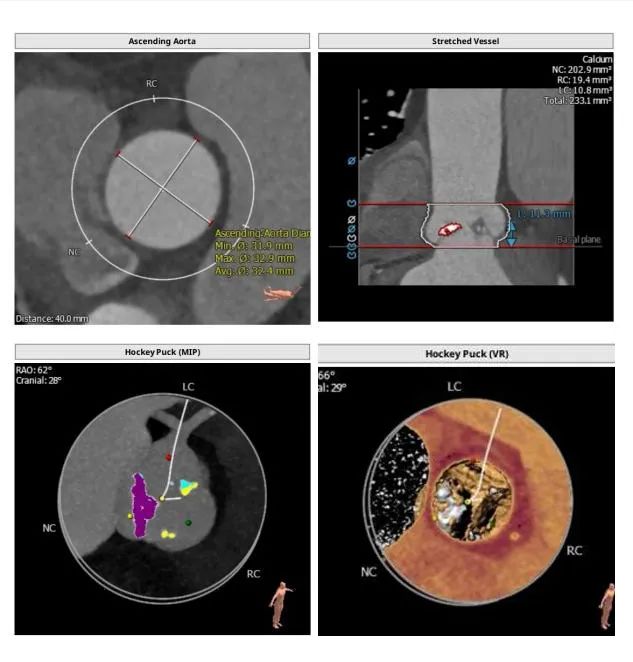

图1 自膨式经导管主动脉瓣置换术瓣膜移位的解剖学预测因素

虚线表示STJ、瓣环和LVOT的平面。箭头表示STJ的高度。AL,瓣环周长/LVOT周长;LVOT,左心室流出道;OR,优势比;STJ,窦管结合部;TAVR,经导管主动脉瓣置换术。

本例患者三叶瓣,重度钙化,左右冠瓣融合,病人瓣环25.2,左室流出道26.9,AL比值=0.93,法氏窦结构长短径均超过30,其中长径35.6,左右冠高度均超过12,瓣叶稍增厚,Stj28.7,距离虚拟瓣环平面23.3mm,综合解剖学因素,同时满足AL比值<0.96以及STJ高度≥23.8mm两个因素,发生瓣中瓣可能性极大。广东省医Tavr团队决定使用Numed25球囊预扩,预装VenusA29号瓣膜进行手术预案。